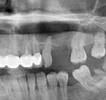

تخرج عام 2014 من كلية طب الأسنان المرموقة بجامعة إسطنبول. وبعد فترة قصيرة، بدأ دراسات الدكتوراه عام 2015 في قسم جراحة الفم والوجه والفكين بجامعة إسطنبول. ركزت أطروحة الدكتوراه الرائدة التي أكملها عام 2020 على "تأثيرات الغرسات السنية ذات الأسطح الدقيقة المتنوعة على الاستقرار الأولي في كثافات العظام المختلفة"، والتي منحت له لقب دكتوراه (Ph.D.) في الفلسفة.

قدم العديد من العروض الشفهية والكتابية في المؤتمرات العلمية داخل وخارج البلاد، مساهماً بشكل فعال في مجال طب الأسنان. وهو معروف بتخصصه وبحثه القوي في زراعة الأسنان وطب الأسنان التجميلي.

علاج الزرعات السنية